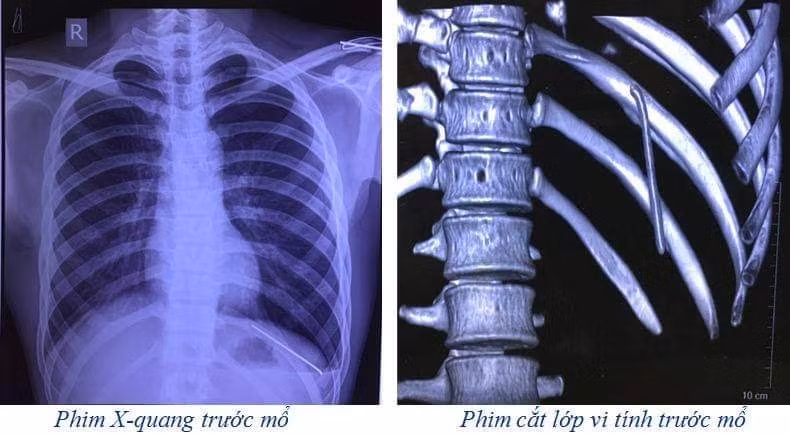

Phim chụp hình ảnh chiếc đinh ở khoang màng phổi.

Sau khi thăm khám, các bác sĩ đã chỉ định chụp X-quang và cắt lớp vi tính lồng ngực. Kết quả phim cắt lớp vi tính lồng ngực cho thấy: dị vật dạng kim khí trong KMP trái, tràn khí KMP trái.